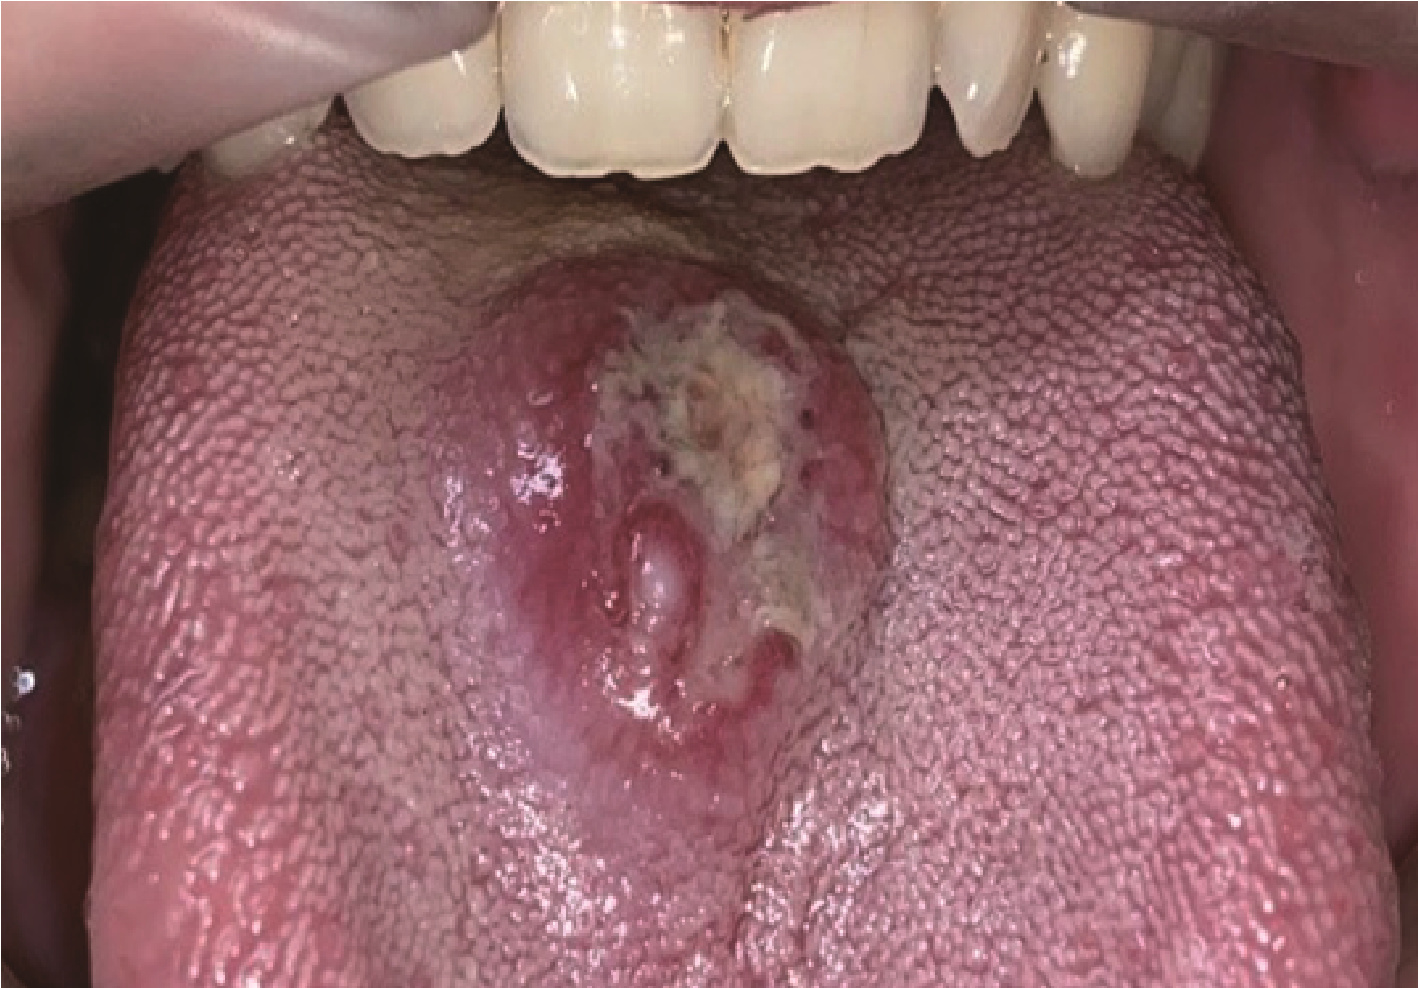

2.2 典型病例2

女性,60岁,因“发现右舌腹溃疡3月”就诊。患者就诊3个月前发现右舌腹黏膜溃疡,初为鱼眼大小,逐渐增大,伴轻度疼痛,未行诊治。追问病史,患者近期精神压力较大,否认食物和药物过敏史,既往史无特殊。专科检查(图 5)发现右舌腹黏膜火山口状溃疡,直径约1.5 cm,表面未见假膜,边界不清(图 5A)。触诊病变质韧,周围组织有硬性浸润,触痛。白细胞计数9.36×109 /L,中性粒细胞比例80.2%;中性粒细胞绝对值7.5×109 /L;嗜酸粒细胞比例0.3%,嗜酸粒细胞绝对值0.03×109 /L。初步诊断为右舌肿物(鳞状细胞癌?)。

图5 病例2,右舌侧缘溃疡

Figure 5 Case 2, an ulcer on the lateral margin of the right tongue

A, appearance of ulcer at the initial diagnosis; B, one week after biopsy, the lesion is smaller than before; C, one month later, the ulcer in the anterior part of the right lingual margin disappeared, and an ulcer appeared in the posterior part of the right lingual margin with rough surface; D, one year later, a mung bean-sized ulcer appeared(arrowhead).

因患者初诊印象疑为鳞状细胞癌,拟切取活检后收入院行手术切除。活检病理报告为黏膜溃疡,表面大片坏死及纤维素渗出,基底血管内皮细胞增生、肥大,呈泡状核,偶见核分裂象。慢性炎症细胞浸润,累及深层肌组织,较多嗜酸粒细胞浸润,倾向于嗜酸性溃疡(图 6)。患者未行治疗。活检后1周,右舌侧缘前部溃疡较前缩小(图 5B),1月后复查,右舌侧缘前部溃疡消失,但在其后部出现溃疡,表面不光滑,无触压疼痛(图 5C)。嘱患者继续观察。1年后复查,右舌侧缘黏膜未见溃疡,仅见少许瘢痕,舌腹黏膜见一个约绿豆大小溃疡(图 5D)。